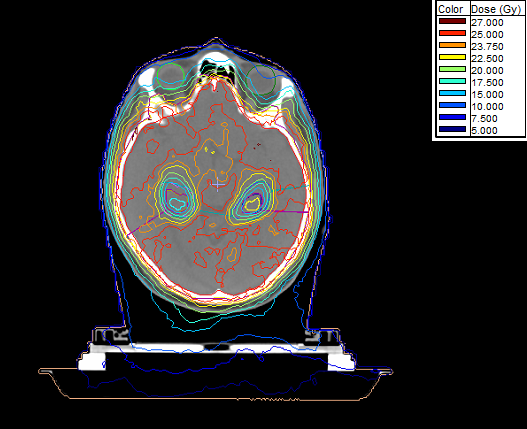

4 arcs used in this plan for PCI in LD-SCLC.

Couch rotations 30°, 90°, 330° for 3 out of 4 arcs.

Wish the lenses were getting less dose...

That headrest is mostly air (if cushion, if plastic it's all air) and isn't seeing as much dose as the TPS is thinking it's seeing because the TPS sees it contoured as body, but yet it must be taking the headrest (and table too it seems) into account in the calc, should we fix that

Indeed, less dose to the lenses would have been nice. However this was a case with very tight constraints at the hippocampi, which had to be met on trial. So, indeed, we had to push for less dose to the hippocampi and "sacrifice" the lenses.

Our dosimetrists contour everything. Couch, any positioning aid, etc. And yes, table and positioning aids do absorbe dose...they are not made of air. Physics have looked into that and run everything through the CT and assigned values to them. I am aware that some clinics/people do not take these into account. We do.